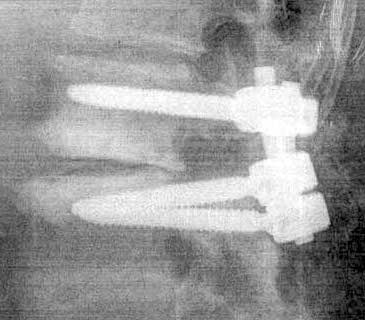

Since 2008, I’d had three levels of vertebrae bolted together. Here are two more views of the original job:

In January, 2013: Bob removed the old fusion hardware and installed bolts and screws at the next level up. You can espy the ball of my still-functional seven-year old bionic hip-joint at lower left. |